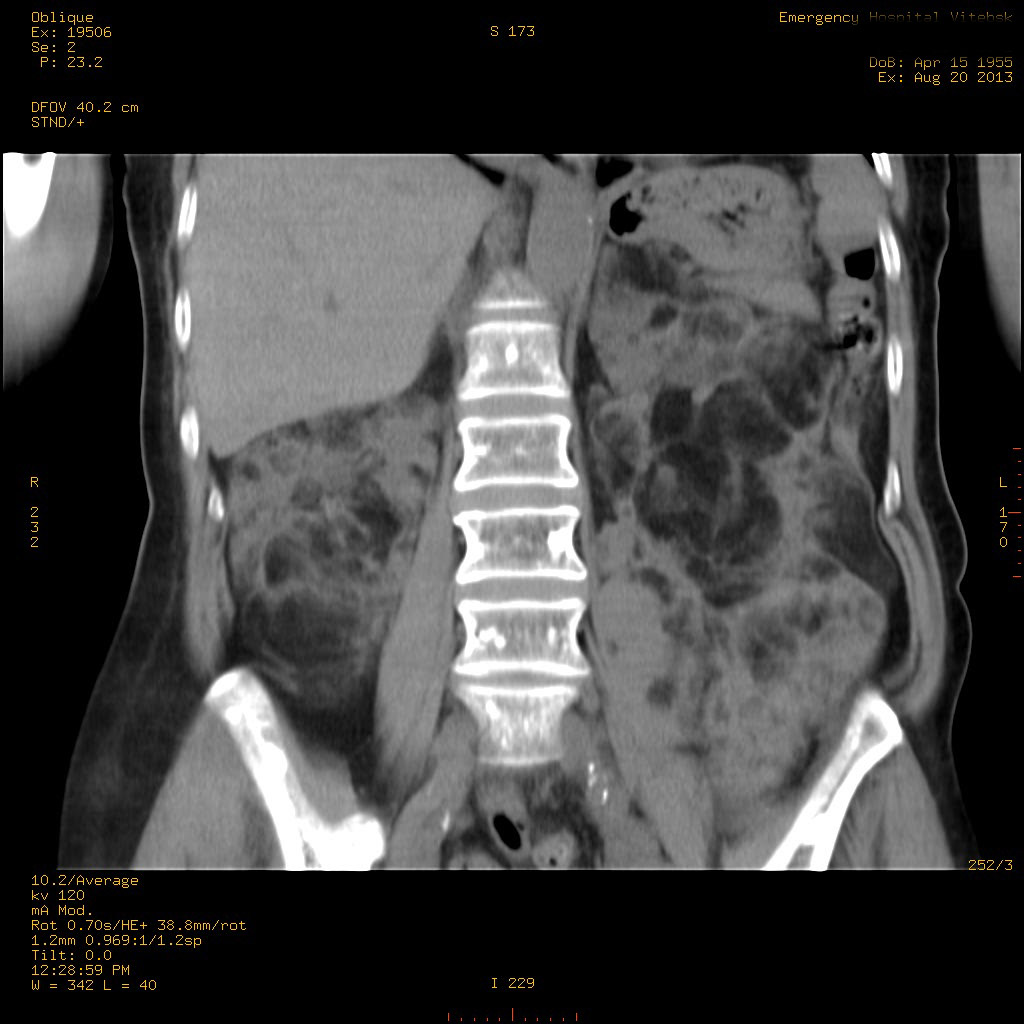

Пожилая женщина с нормальными мочевиной и креатинином.

se000.jpg

se001.jpg

se002.jpg

se003.jpg

Ангиомиолипоматоз почек , думаю компонент туберозного склероза.

Да, туберозный склероз.

Случай консультирован на кафедре радиологии Католического университета г.Лёвен (Бельгия) - зав каф. профессор Р.Оуен.